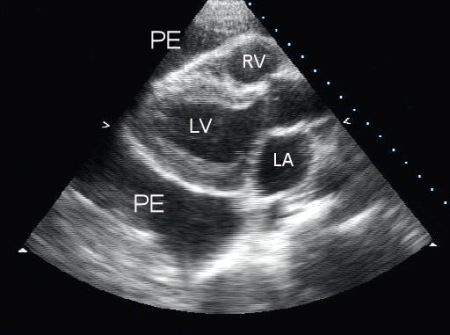

Assessment of pericardial effusion

Parasternal long-axis view of a pericardial effusion (PE); LA = left atrium, LV = left ventricle, RV = right ventricle

From the collection of Dr Rajdeep Khattar